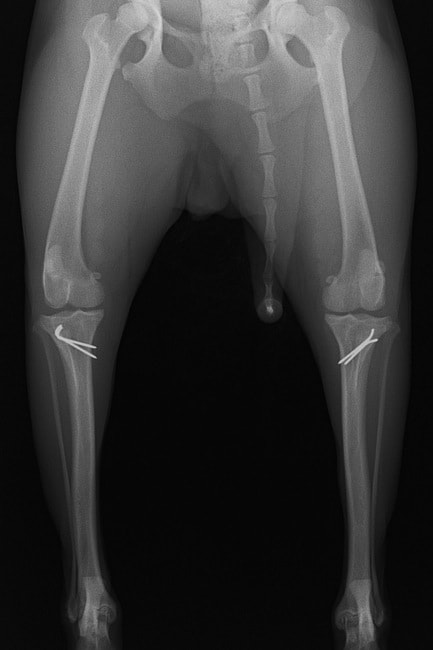

■ 症例20 ポメラニアン 8ヶ月 1.8kg

左右膝蓋骨脱臼 グレードⅢ

2ヶ月前から間欠的跛行が認められ、両膝の膝蓋骨脱臼整復術を行った。

手技は縫工筋及び内側広筋の解放、脛骨粗面の外側転位、滑車ブロック形造溝術、内外側関節包の縫縮を選択し実施した。

右側の膝蓋骨脱臼は上記手技で整復されたものの、左側はそれのみでは膝蓋骨が浮く様子が認められた。その為、PDS縫合糸にて膝蓋靱帯を1糸のみ縫合し、靱帯の縫縮を行った。

膝蓋骨脱臼は膝関節における膝蓋骨の内外側の脱臼と定義されるが、時として単純な内外の脱臼ではなく、膝蓋骨が大きく前方に浮き上がるように脱臼する場合がある。特にトイプードルやポメラニアンといった犬種に多く認められる。

内側脱臼に加えて前方への浮き上がりを矯正する為に、従来より脛骨粗面転移により膝蓋靭帯を外方と下方に引っ張り、固定する方法を選択する。膝蓋骨の前方への浮き上がりが軽度の場合は、従来法ではなく関節包の縫縮で対応していた。しかし、一部の症例で膝蓋骨の動きが悪くなり伸展機構が円滑に機能せずロボット様歩行になるケースがあった。

その為、膝蓋靭帯自体を縫縮する方法を採用した。この方法により、膝関節の伸展機構を妨げず膝蓋骨の軽度の浮きを矯正することが可能となった。

本症例の経過は良好である